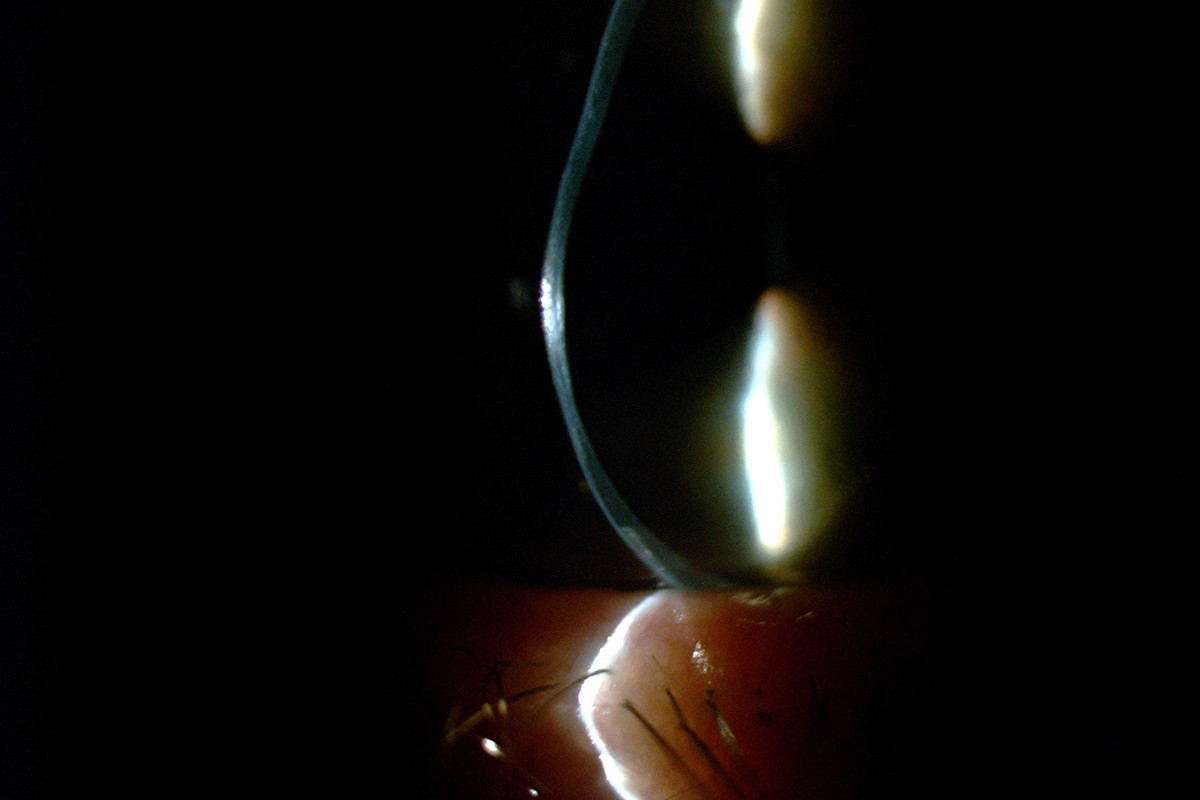

Fenêtre organique